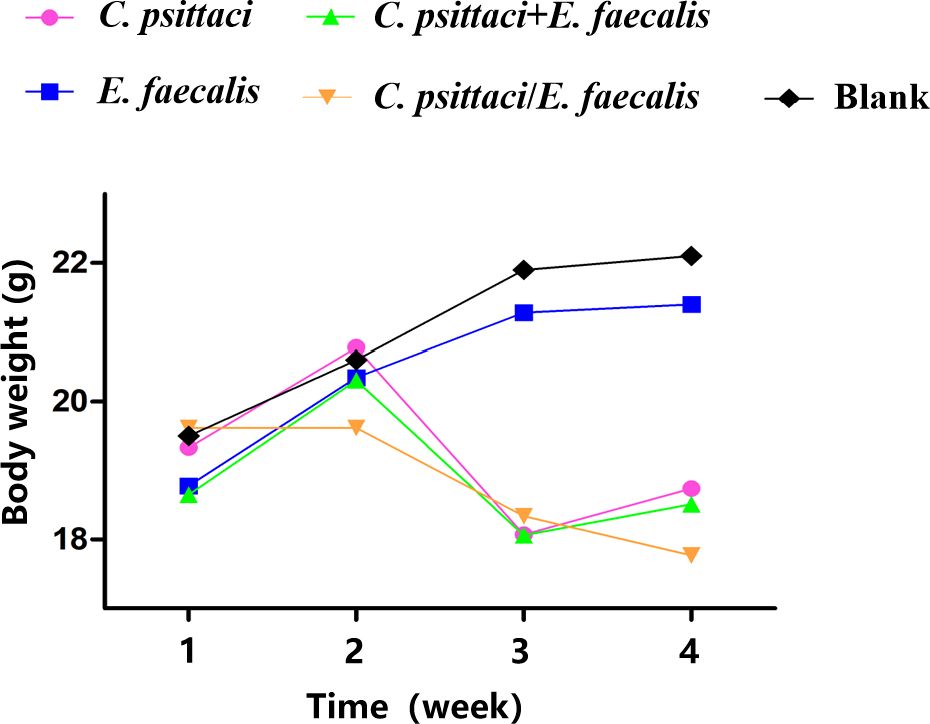

Clinically, mice infected primarily with C. psittaci, followed by E. faecalis (C. psittaci/E. faecalis) inoculation or C. psittaci infection alone, showed ruffled feathers, inactivity, poor appetite, and low weight; especially severe signs were found in female mice compared to male mice. For body weights, those of the C. psittaci/E. faecalis group, C. psittaci alone group, and C. psittaci+E. faecalis group were lower 1 week later. More importantly, mouse body weights declined during the observation in the C. psittaci/E. faecalis group (p < 0.01). However, no decrease was found in the E. faecalis alone group and the control group (Figure 6).

Figure 6. Body weight after inoculation with coinfection with Chlamydia psittaci or Enterococcus faecalis in mice. Two weeks post-infection, the body weight levels of the C. psittaci/E. faecalis group were lower than those of the other three groups (p < 0.01). No statistical difference was found in the E. faecalis alone group and the control group. The differences were analyzed using ANOVA (p < 0.05, p < 0.01).